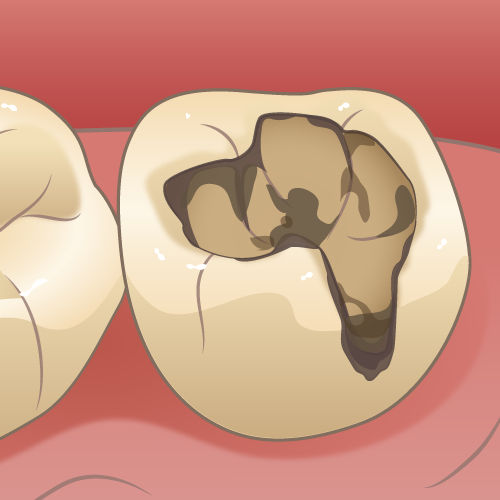

⑥ 前回詰めた綿花の状態を確認して、良い状態なら、「根管充填剤」(マスターポイント・アクセサリーポイント)というお薬を、余分な空間がないように根っこに詰めます。

⑥ 前回詰めた綿花の状態を確認して、良い状態なら、「根管充填剤」(マスターポイント・アクセサリーポイント)というお薬を、余分な空間がないように根っこに詰めます。 Q1.痛みはありますか?

Q1.痛みはありますか? ② 次に、「根管長測定器」という機械を使い、根っこの長さを正確に測ります。

② 次に、「根管長測定器」という機械を使い、根っこの長さを正確に測ります。

⑤ 次に、仮詰めをします。

⑤ 次に、仮詰めをします。 虫歯が神経まで達して炎症を起こしているので、人によってはズキズキとした痛みを感じる方もいます(>_<)

虫歯が神経まで達して炎症を起こしているので、人によってはズキズキとした痛みを感じる方もいます(>_<)